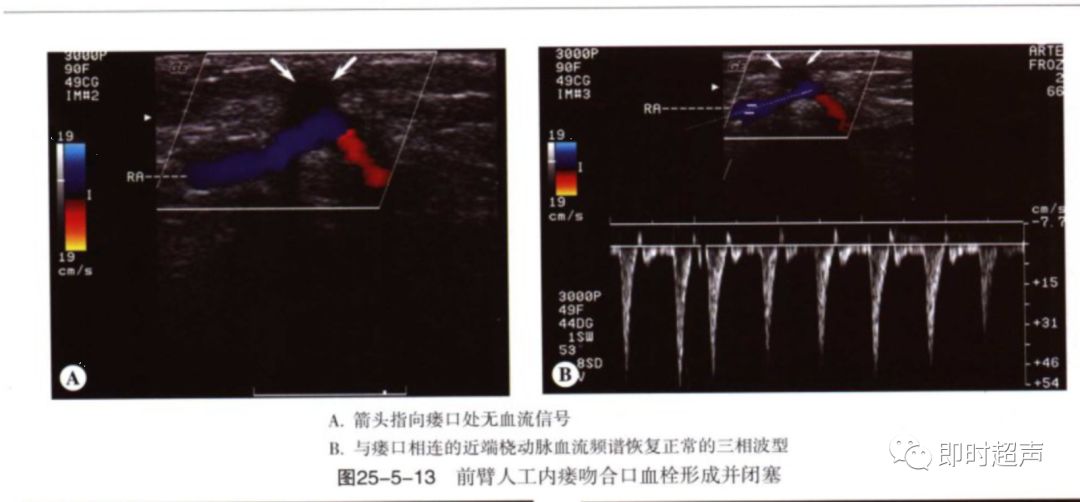

血栓:血栓与狭窄密切相关,常发于静脉侧,静脉管腔压瘪可除外血栓形成。闭塞处可见彩色多普勒血流中断,频谱多普勒信号消失。流入道动脉呈高阻频谱改变。

超声表现:多普勒分析:狭窄处直接征象:PSV>4m/s(直径狭窄率50%以上),间接征象:供血动脉或肱动脉呈高阻波形,血流量减少。

肱动脉及流入道动脉见到高阻动脉血流频谱提示有重度狭窄。